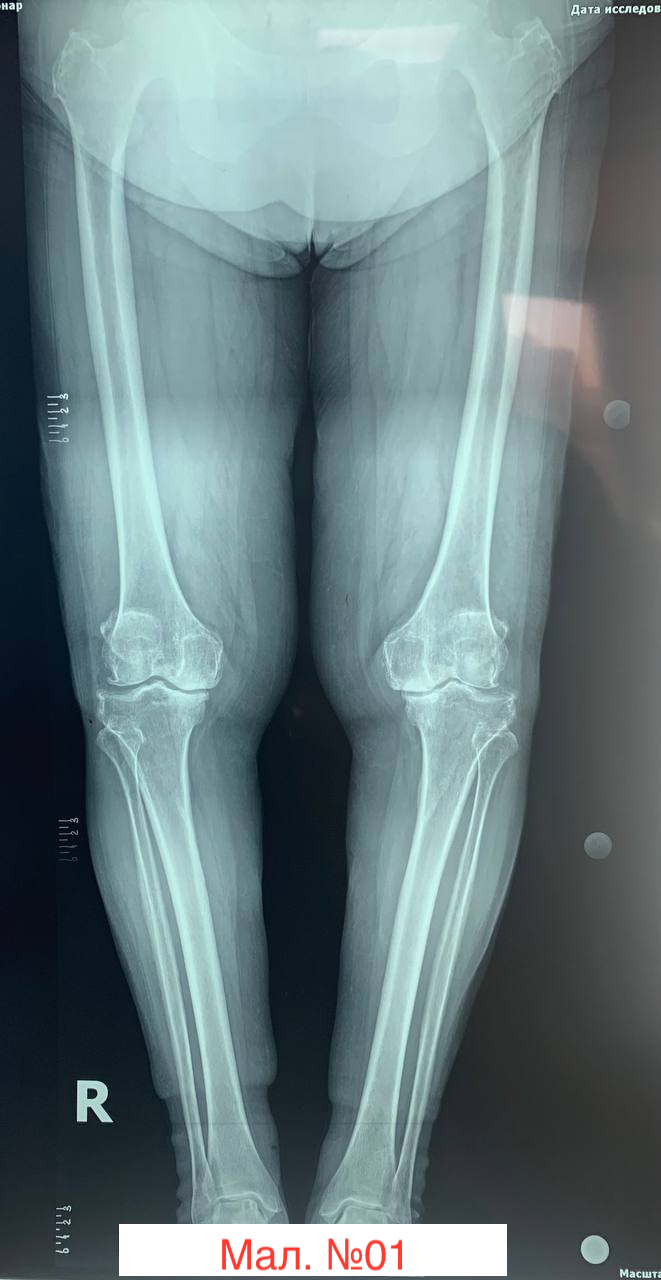

photo_2023-12-13 17.20.25